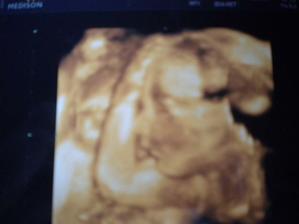

Ukázal nám zase vnitřní orgány a tatínkovi taky důkaz, že maminka opravdu nekecá a Jáchym bude! 😉 A prtě váží cca 2,7kg, tak to vypadá, že bude váhově podobně jako Ameli.